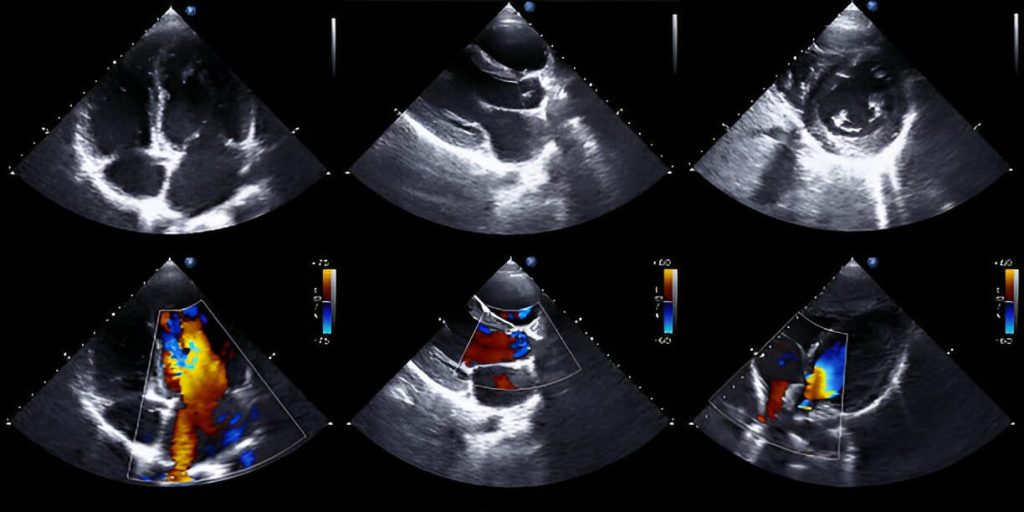

2-D Echocardiography is a powerful diagnostic tool that uses ultrasound technology to create detailed images of the heart’s structure and function. At Shree Shiv Digital X-ray & Sonography (Color Doppler) Clinic, we offer comprehensive 2-D echocardiography services to help diagnose and monitor a wide range of heart conditions, from valve abnormalities to congenital heart defects. Our advanced equipment and experienced cardiologists ensure that you receive the most accurate and reliable results possible.

One of the primary benefits of 2-D echocardiography is its ability to provide real-time images of the heart’s chambers, valves, and blood flow. This allows our cardiologists to assess the heart’s pumping function, detect abnormalities, and evaluate the severity of conditions such as heart failure, cardiomyopathy, or pericardial effusion. It is also commonly used to diagnose valve disorders, such as mitral valve prolapse or aortic stenosis, and to monitor the progression of these conditions over time.